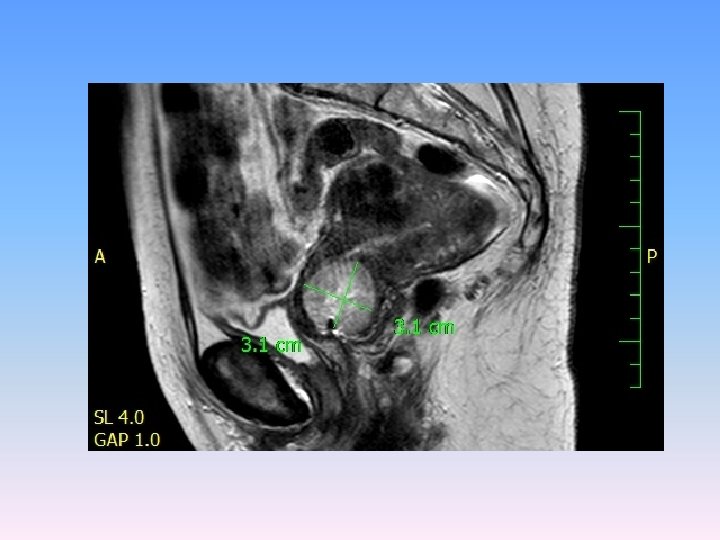

MRI V oblasti cervixu expanzivní útvar 3 cm v průměru s odlišným signálem oproti okolní děloze a vlastním myomům, expanze má vyšší obsah vody. Zaujímá celý vnitřní prostor cervixu, podél expanze zůstává tenký lem tkáně šíře 3 mm. Nikde nepřechází expanze z cervixu na okolní struktury.

Děložní tělo, parametria a poševní manžeta bez nádorové infiltrace Téměř celé děložní hrdlo infiltrované strukturami Karcinosarkomu (M 8990/32), kdy přibližně z poloviny je novotvar tvořen strukturami sarkomovými, z poloviny strukturami méně diferencovaného endometroidního adenokarcinomu. Intaktní tkáň na povrchu cervixu šíře 3 mm. Invaze do krevních ani lymfatických cév nezastižena. Omentum, appendix, pánevní a paraaortální lymfatické uzliny (36) bez maligní infiltrace